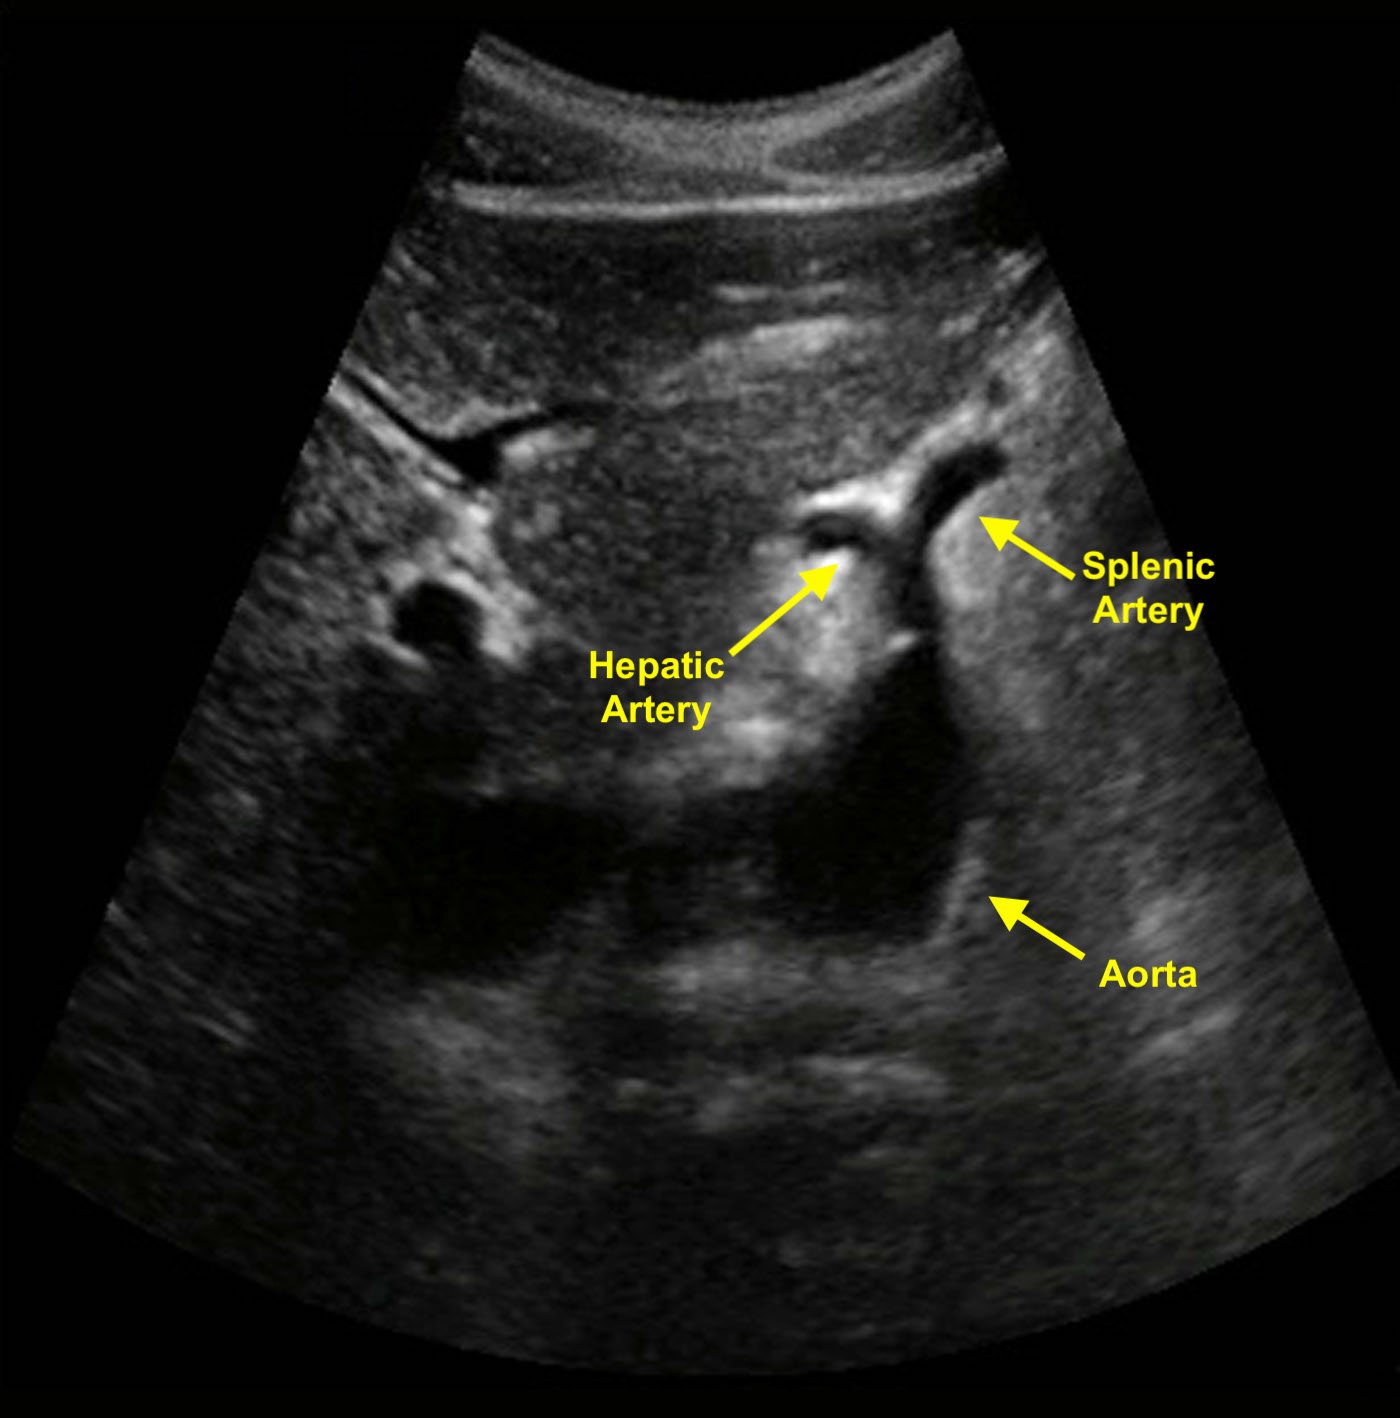

- Celiac trunk is first major vessel to arise from the abdominal aorta in the midline anteriorly (Figure 1). This short vessel can often be seen in the transverse plane, dividing in a “wide Y.” This sonographic view is known as the “seagull sign.”

- Fork on patient’s right is common hepatic artery.

- Fork on patient’s left is splenic artery.

- Figure 1. Transverse image of the aorta shows a classic example of the seagull sign. The celiac trunk branches into the hepatic and splenic arteries.